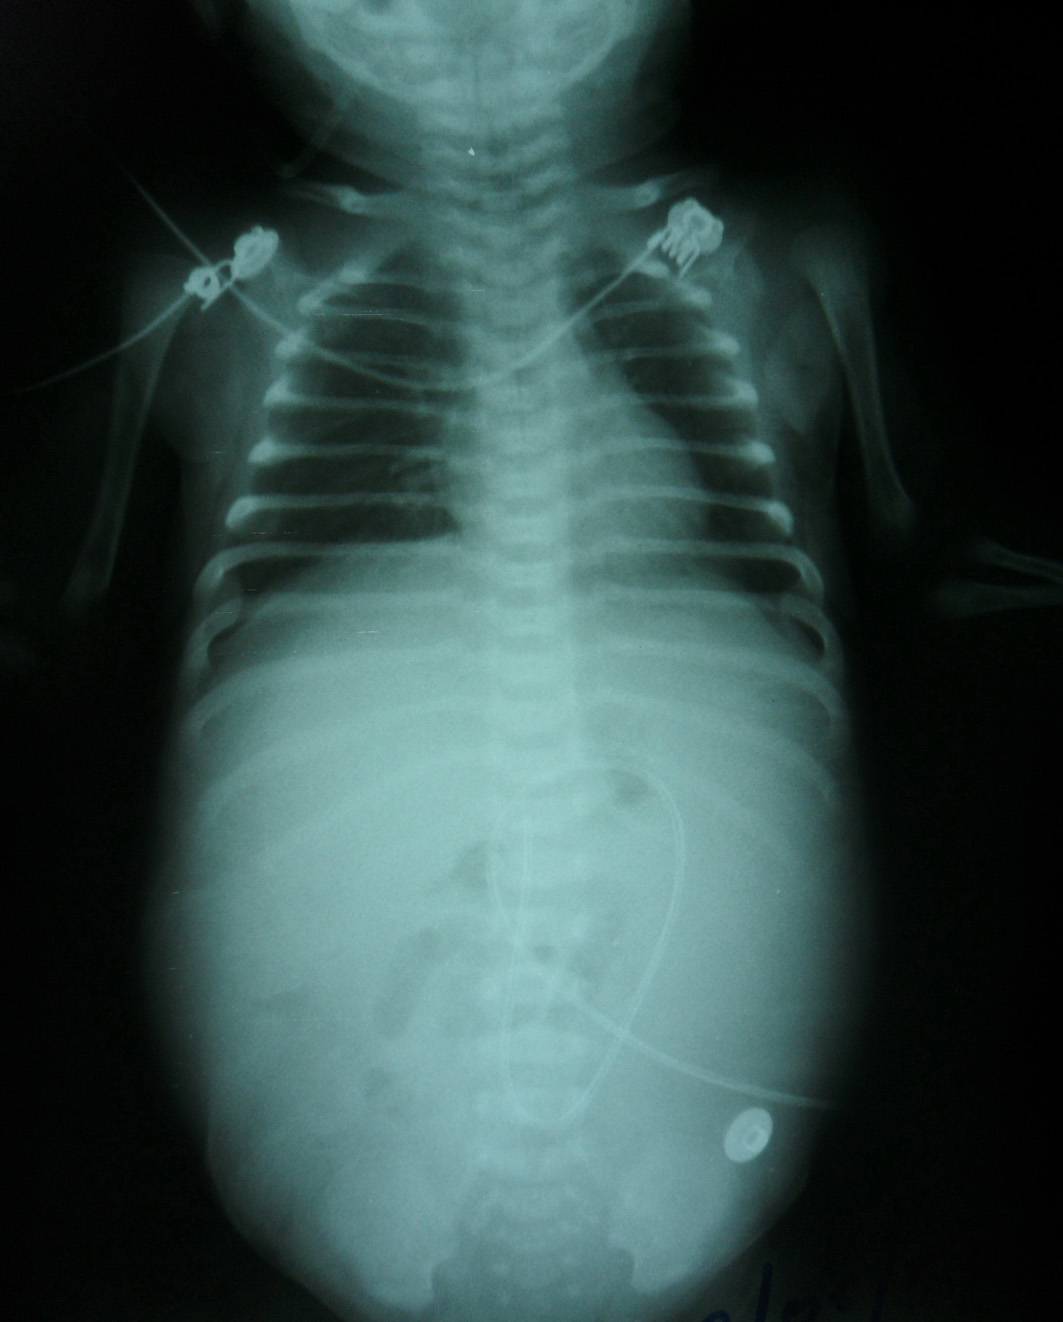

Vital signs were stable. On physical examination, there was marked abdominal distension with hypoactive or reduced bowel sound, with positive fluid thrill and shifting dullness. Confirmatory plain abdominal roenterography showed abdominal distension with diffuse increase density and poor definition of soft tissue shadows; ascites was suspected (Fig. 1). Ultrasonography of abdomen depicted massive ascites with other normal abdominal findings. Baby was on Nil per os/Nil per oral (NPO) with abdominal tapping as a therapy. Twenty milliliters of milky turbid fluid came out while tapping and it was examined. Examination revealed total cell count as 885 cells/mm3, WBC as 801 cells/mm3, RBC as 84 cells/mm3, PMN as 81 %, Monocytes as 1% and Macrophage as 18 %. Ascitic fluid examination revealed no organism found by gram strain and culture. Ascites biochemistry measurement revealed that protein was 0.76 g/dL, Serum ascites albumin gradient (SAAG) 3.87, (serum Alb = 4.63 g/dL, serum globulin = 2.8 g/dL), fluid sugar 282 mg/dL (blood sugar 104), fluid LDH 145 U/L, fluid cholesterol 15 mg/dL, fluid triglyceride (TG) 3332 (Serum TG 191).

![]() Click for large image | Figure 1. Plain abdominal film on day 11 of life revealed abdominal distension with diffuse increase density and poor definition of the soft tissue shadows. |